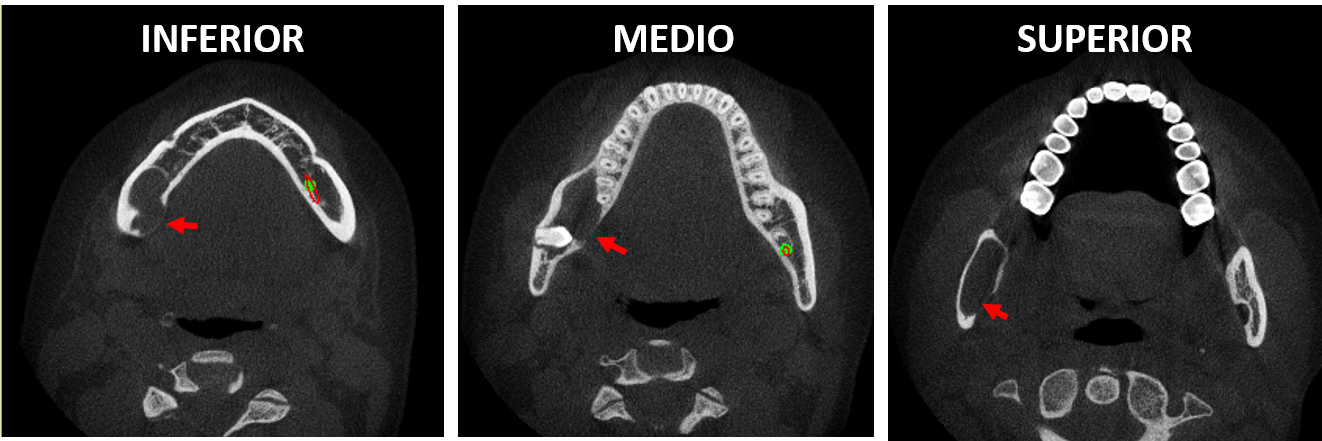

Fig.3

En cortes sagitales (Fig.2) y cortes se observa el órgano dentario 48 en aparente posición transversal con las raíces (en formación) orientadas hacia la tabla externa de la rama mandibular y la corona orientada hacia la tabla ósea interna. Asi mismo, se observa el marcado adelgazamiento de la cortical interna de la mandíbula, en los cortes axiales (Fig.3. Flechas rojas) a nivel de la rama ascendente y el cuerpo mandibular.